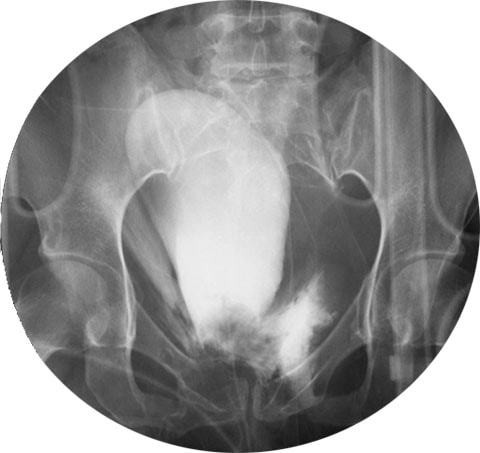

Врач-уролог изучает снимки ребенка, полученные при рентгене мочевого пузыря. В норме наполненный орган у детей имеет четкие контуры и грушевидную форму. Восходящая цистография помогает выявить:

- камни и песок;

- инородные предметы;

- уретероцеле (опущение мочеточника);

- туберкулезные процессы;

- опухоли;

- травмы — при них контраст виден за пределами органа;

- нейрогенный мочевой пузырь — на снимке увеличен;

- слабость сфинктера, имеющую вид языковидного забрасывания рентгеноконтрастного вещества в заднюю часть уретры;

- остаточную урину в пузыре после самостоятельного мочеиспускания;

- дивертикулы (мешковидные выпячивания стенки органа), которые на цистограмме выглядят как добавочная полость сбоку от мочевого пузыря.

При выявлении тяжелых пороков и разрывов мочевого пузыря пациента готовят к операции. Инородные тела, камни и опухоли ликвидируют способом, выбранным врачом. При обнаружении воспалительных болезней мочеполовой системы назначают лечение народными средствами и медикаментами.

Восходящая или ретроградная цистография считается традиционным способом проведения обследования. Рентгеновские снимки мочевого пузыря выполняются под разными углами после его опорожнения, обезболивания мочеиспускательного канала и заполнения контрастным веществом через уретральный катетер. Длительность процедуры составляет от 30 до 60 минут.

Популярным методом исследования является ретроградная микционная цистография. Ее отличие от традиционного обследования состоит в получении снимков мочевого пузыря не только после заполнения контрастным веществом, но и в процессе совершения акта мочеиспускания.

Полученные изображения позволяют более точно диагностировать пузырно-мочеточниковый рефлюкс.